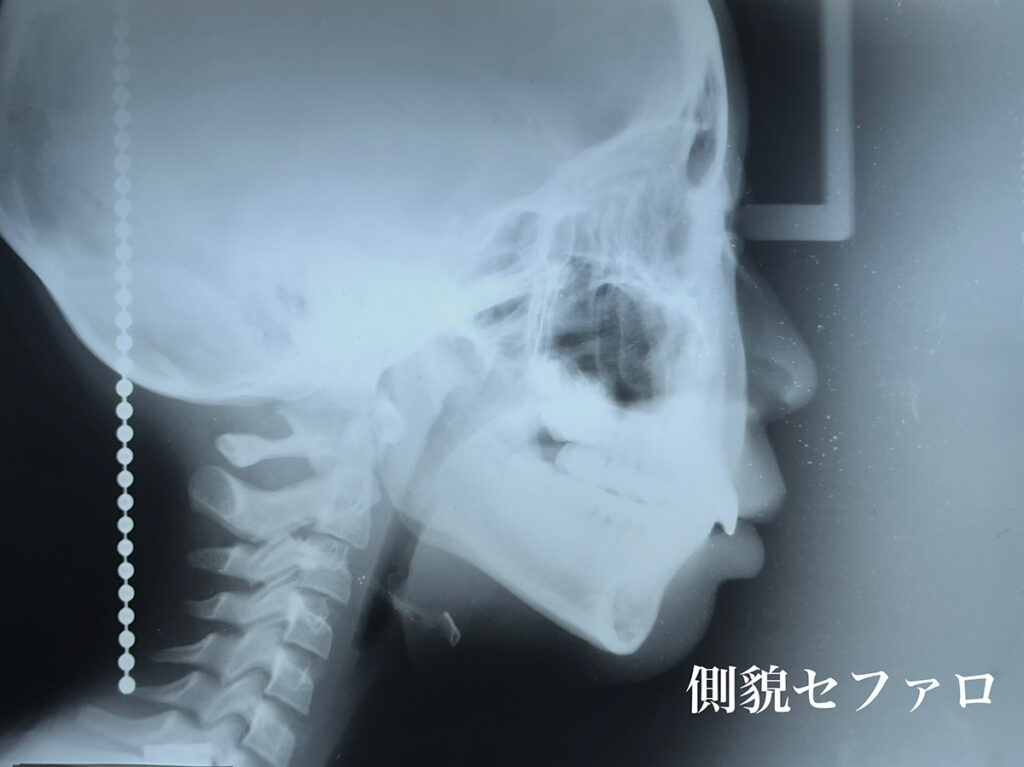

レントゲン所見においては、矯正歯科治療においてセファロ写真分析は欠かせません。

しかし、それだけでは情報量としては不足だと考えています。

私はレントゲンメーカーの協力によって特注の機器を製作していただき臨床に活用しております。頭蓋骨の3軸方向からの分析し、骨の変形とともに、頭蓋骨と下顎骨との位置的関係について精査し、正しい咬み合わせでの歯科矯正治療を確実に行います。